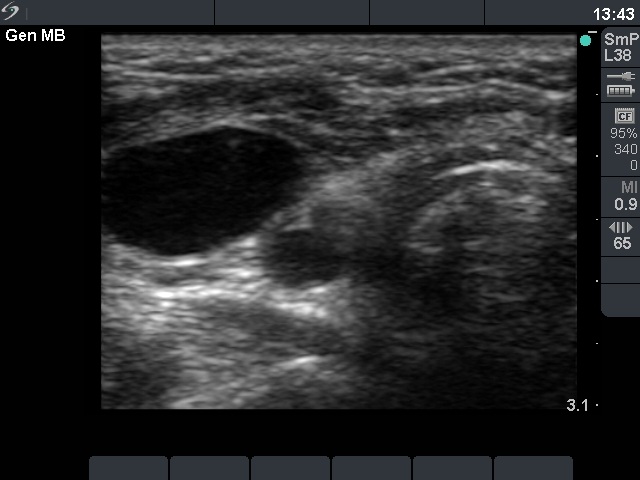

Ultrasound. Except for inconspicuous, moderately hypoechogenic lesion on the ventral wall of the carotid artery, neither thyroid parenchyma in the thyroid beds nor suspicious neck lymph nodes were found. The moderately hypoechoic lesion has bright echogenic granules and was avascular.

Cytology resulted in Hürthle-cell tumor.